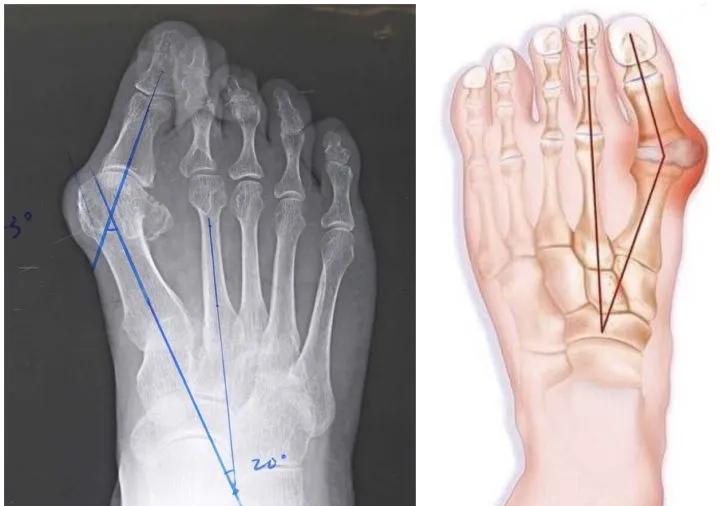

长期穿高跟鞋容易导致拇趾外翻,如果经常穿尖头的高跟鞋情况会尤为厉害。行走时改变了足部均匀承受体重的状态,全身的重量转移到前脚掌。

为了维持足部的稳定,足内侧的拇收肌和拇短屈肌紧张收缩,牵扯拇趾外翻,并且拇长伸肌肌腱滑向拇趾外侧,促使第1跖骨内翻,促使拇外翻的形成。

不仅是脚的畸形,影响外观,而且会因为摩擦,引起发炎,带来疼痛。